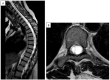

Background: Syringomyelia is a complex neurological disorder characterized by a fluid-filled cavity (syrinx) within the spinal cord, frequently resulting from altered cerebrospinal fluid (CSF) dynamics. While its clinical manifestations are diverse, orthopedic complications such as scoliosis, pes cavus, and Charcot arthropathy may represent early diagnostic clues yet are often under-recognized. Methods: This comprehensive review synthesizes the current literature on the pathophysiology, clinical presentation, diagnostic strategies, and management approaches of syringomyelia, with a specific emphasis on its orthopedic manifestations. Additionally, we present a detailed case of neuropathic shoulder arthropathy associated with advanced syringomyelia. Results: Orthopedic involvement in syringomyelia includes progressive spinal deformities and neurogenic joint destruction, particularly affecting the shoulder and elbow. Scoliosis is frequently observed, especially in association with Chiari malformations, and may precede neurologic diagnosis. Charcot joints result from impaired proprioception and protective sensation. The case presented illustrates the diagnostic challenges and therapeutic dilemmas in managing advanced neuro-orthopedic complications in syringomyelia. Conclusions: Syringomyelia should be considered in the differential diagnosis of atypical musculoskeletal presentations. Early recognition and multidisciplinary management are essential to prevent irreversible orthopedic sequelae. Conservative treatment remains the mainstay in stable cases, while surgery is reserved for progressive disease. Orthopedic assessment plays a pivotal role in the diagnostic pathway and long-term care of affected patients.